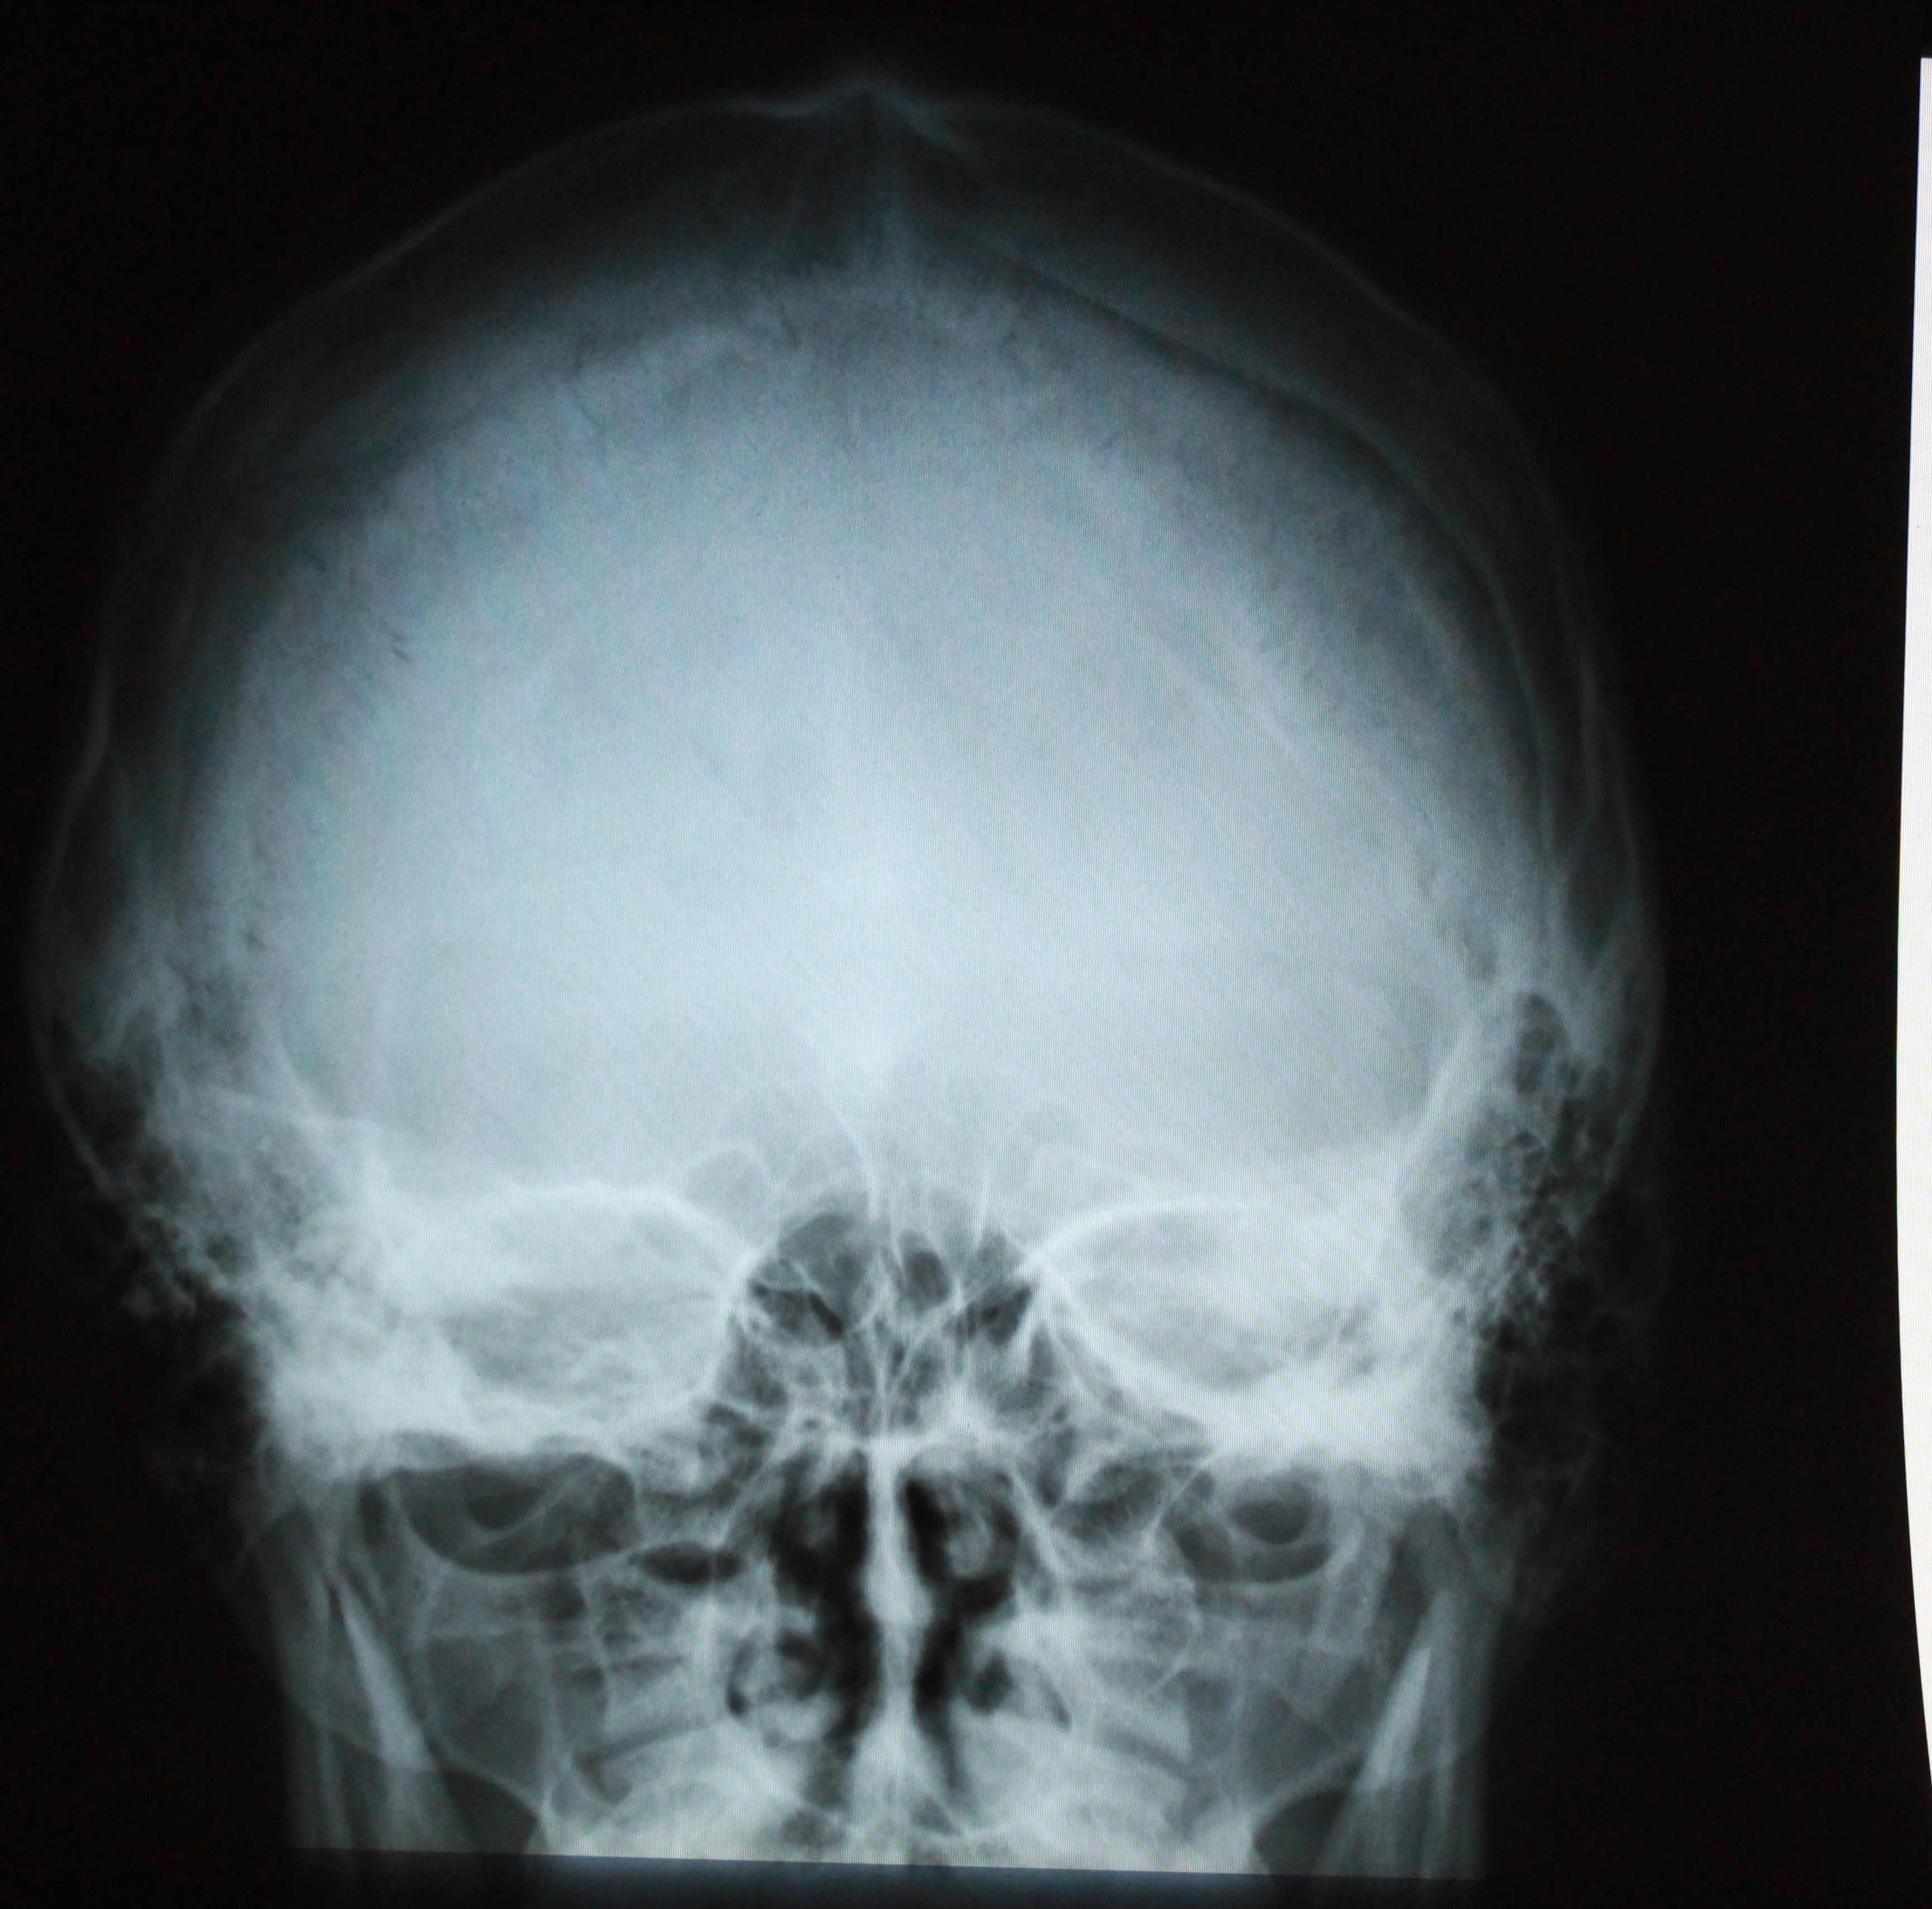

Анатомия мозга: Рентгеновские снимки для презентаций